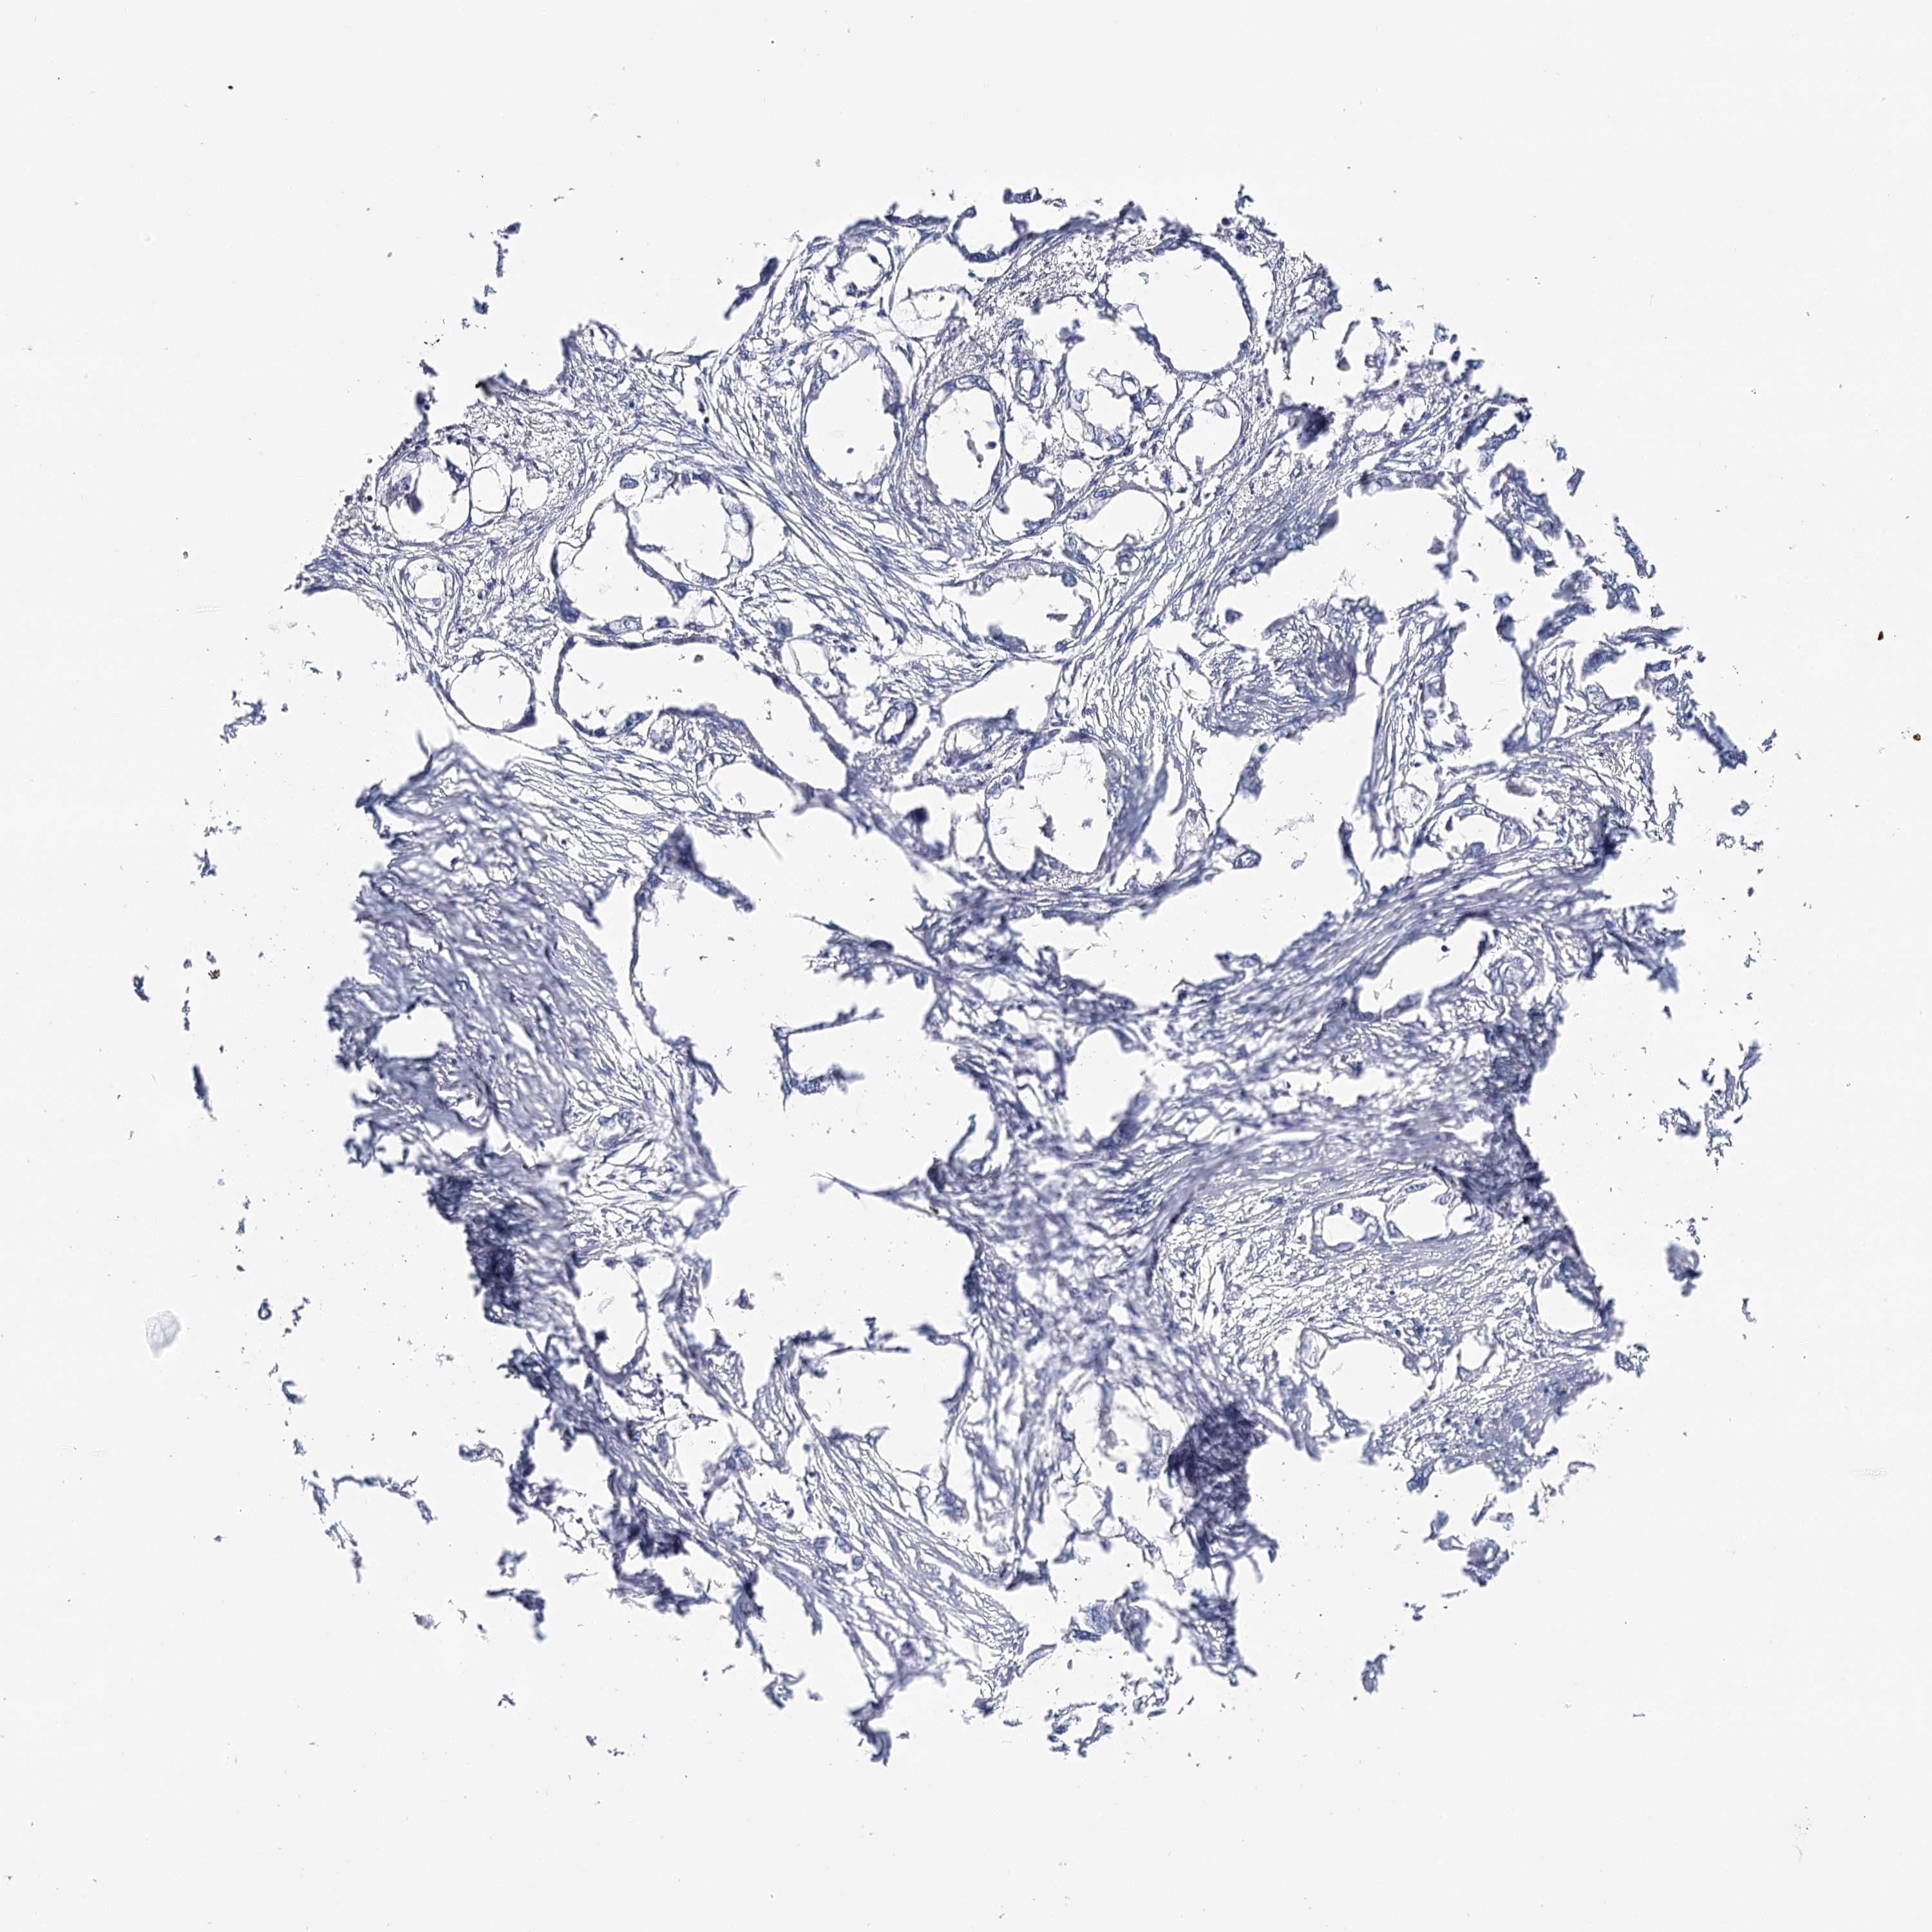

ENDOMETRIAL CANCER - Protein expressioni

A mouse-over function shows sample information and annotation data. Click on an image to view it in a full screen mode. Samples can be filtered based on level of antibody staining by selecting one or several of the following categories: high, medium, low and not detected. The assay and annotation is described here.

Note that samples used for immunohistochemistry by the Human Protein Atlas do not correspond to samples in the TCGA dataset.

Antibody stainingi

Antibody staining in the annotated cell types in the current human tissue is reported as not detected, low, medium, or high, based on conventional immunohistochemistry profiling in selected tissues. This score is based on the combination of the staining intensity and fraction of stained cells.

Each image is clickable and will lead to virtual microscopy that enables deeper exploration of all samples and also displays staining intensity scores, fraction scores and subcellular localization as well as patient and tissue information for each sample.

Antibody CAB002973

Antibody CAB039238

Antibody CAB039239

Antibody CAB072876

Staining

High

Medium

Low

Not detected

Intensity

Strong

Moderate

Weak

Negative

Quantity

>75%

75%-25%

<25%

None

Location

Nuclear

Cytoplasmic/membranous

Cytoplasmic/membranous,nuclear

Adenocarcinoma, NOS

Neoplasm, malignant, NOS

Adenocarcinoma, metastatic, NOS